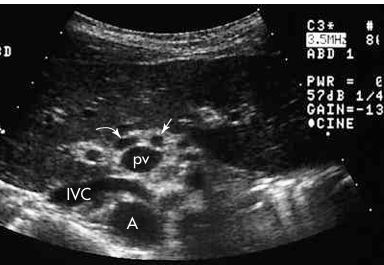

1. Portal Vein

2. Common Bile Duct

3. Gallbladder

arrow: MLF

curved arrow: portal vein

arrow: CBD

curved arrow: CBD

arrow: HA